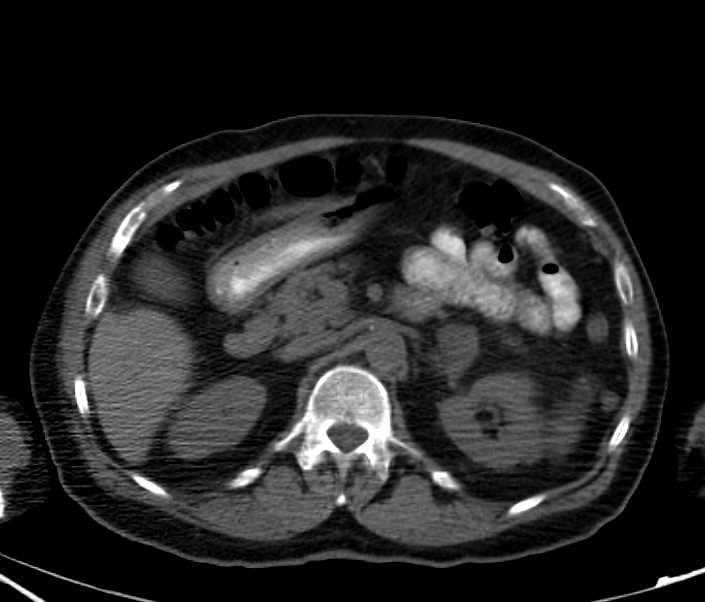

End Stage Renal Disease with Extensive Vascular Disease in Abdomen